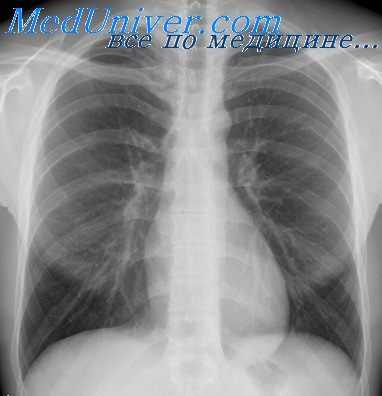

Планарное изображение перфузии миокарда

До широкого распространения томографических методов визуализации перфузии (например, ОФЭКТ) стандартным считали планарное исследование. При пленарной визуализации после введения РФП и его фиксации в миокарде с помощью гамма-камеры получают три отдельных двухмерных изображения. Стандартными проекциями являются передняя, левая передняя косая и боковая. При пленарном исследовании проекции стандартные, поэтому врач, выполняющий процедуру, должен использовать дополнительные проекции для оценки регионарных нарушений. Напротив, вследствие того, что при ОФЭКТ срезы реконструируются перпендикулярно и параллельно определенной продольной оси, на ОФЭКТ-изображения не влияют индивидуальные особенности расположения сердца, и они более ориентированы на отображение и интерпретацию.

Преимуществом планарной визуализации перед ОФЭКТ является простота. Каждая из трех проекций может быть получена за 5-8 мин, причем пациент лежит на столе с руками, вытянутыми вдоль тела. Планарная визуализация менее зависима от движений пациента по сравнению с ОФЭКТ. Обработка планарных исследований не столь сложна и трудоемка, как при ОФЭКТ, при которой существует много причин для потенциальных ошибок и артефактов. Однако изначальная двухмерная природа планарных изображений ведет к тому, что в каждой из стандартных проекций присутствует существенное перекрывание зон миокарда и меньшая возможность определения небольших и не очень выраженных дефектов перфузии. Более стандартная ориентация при ОФЭКТ обеспечивает легкость в определении локализации нарушений перфузии.

Изначально данные о чувствительности и специфичности визуализации при ИБС, как и прогностическая ценность, рассчитывались по результатам планарных исследований, а затем были перепроверены данными ОФЭКТ. В современной практике планарная визуализация может быть использована у пациентов, которые не могут выдержать длительного статического положения, необходимого для ОФЭКТ, и у тех, кто испытывает неудобства при нахождении громоздкого детектора гамма-камеры в непосредственной близости от тела, а также у пациентов, размеры и масса тела которых превышают возможности ОФЭКТ-систем.

Методы количественного анализа, например круговой профиль, изначально были созданы для планарных исследований. Многие литературные источники свидетельствуют о повышении чувствительности количественной обработки планарных исследований при диагностике ИБС с многососудистым поражением.